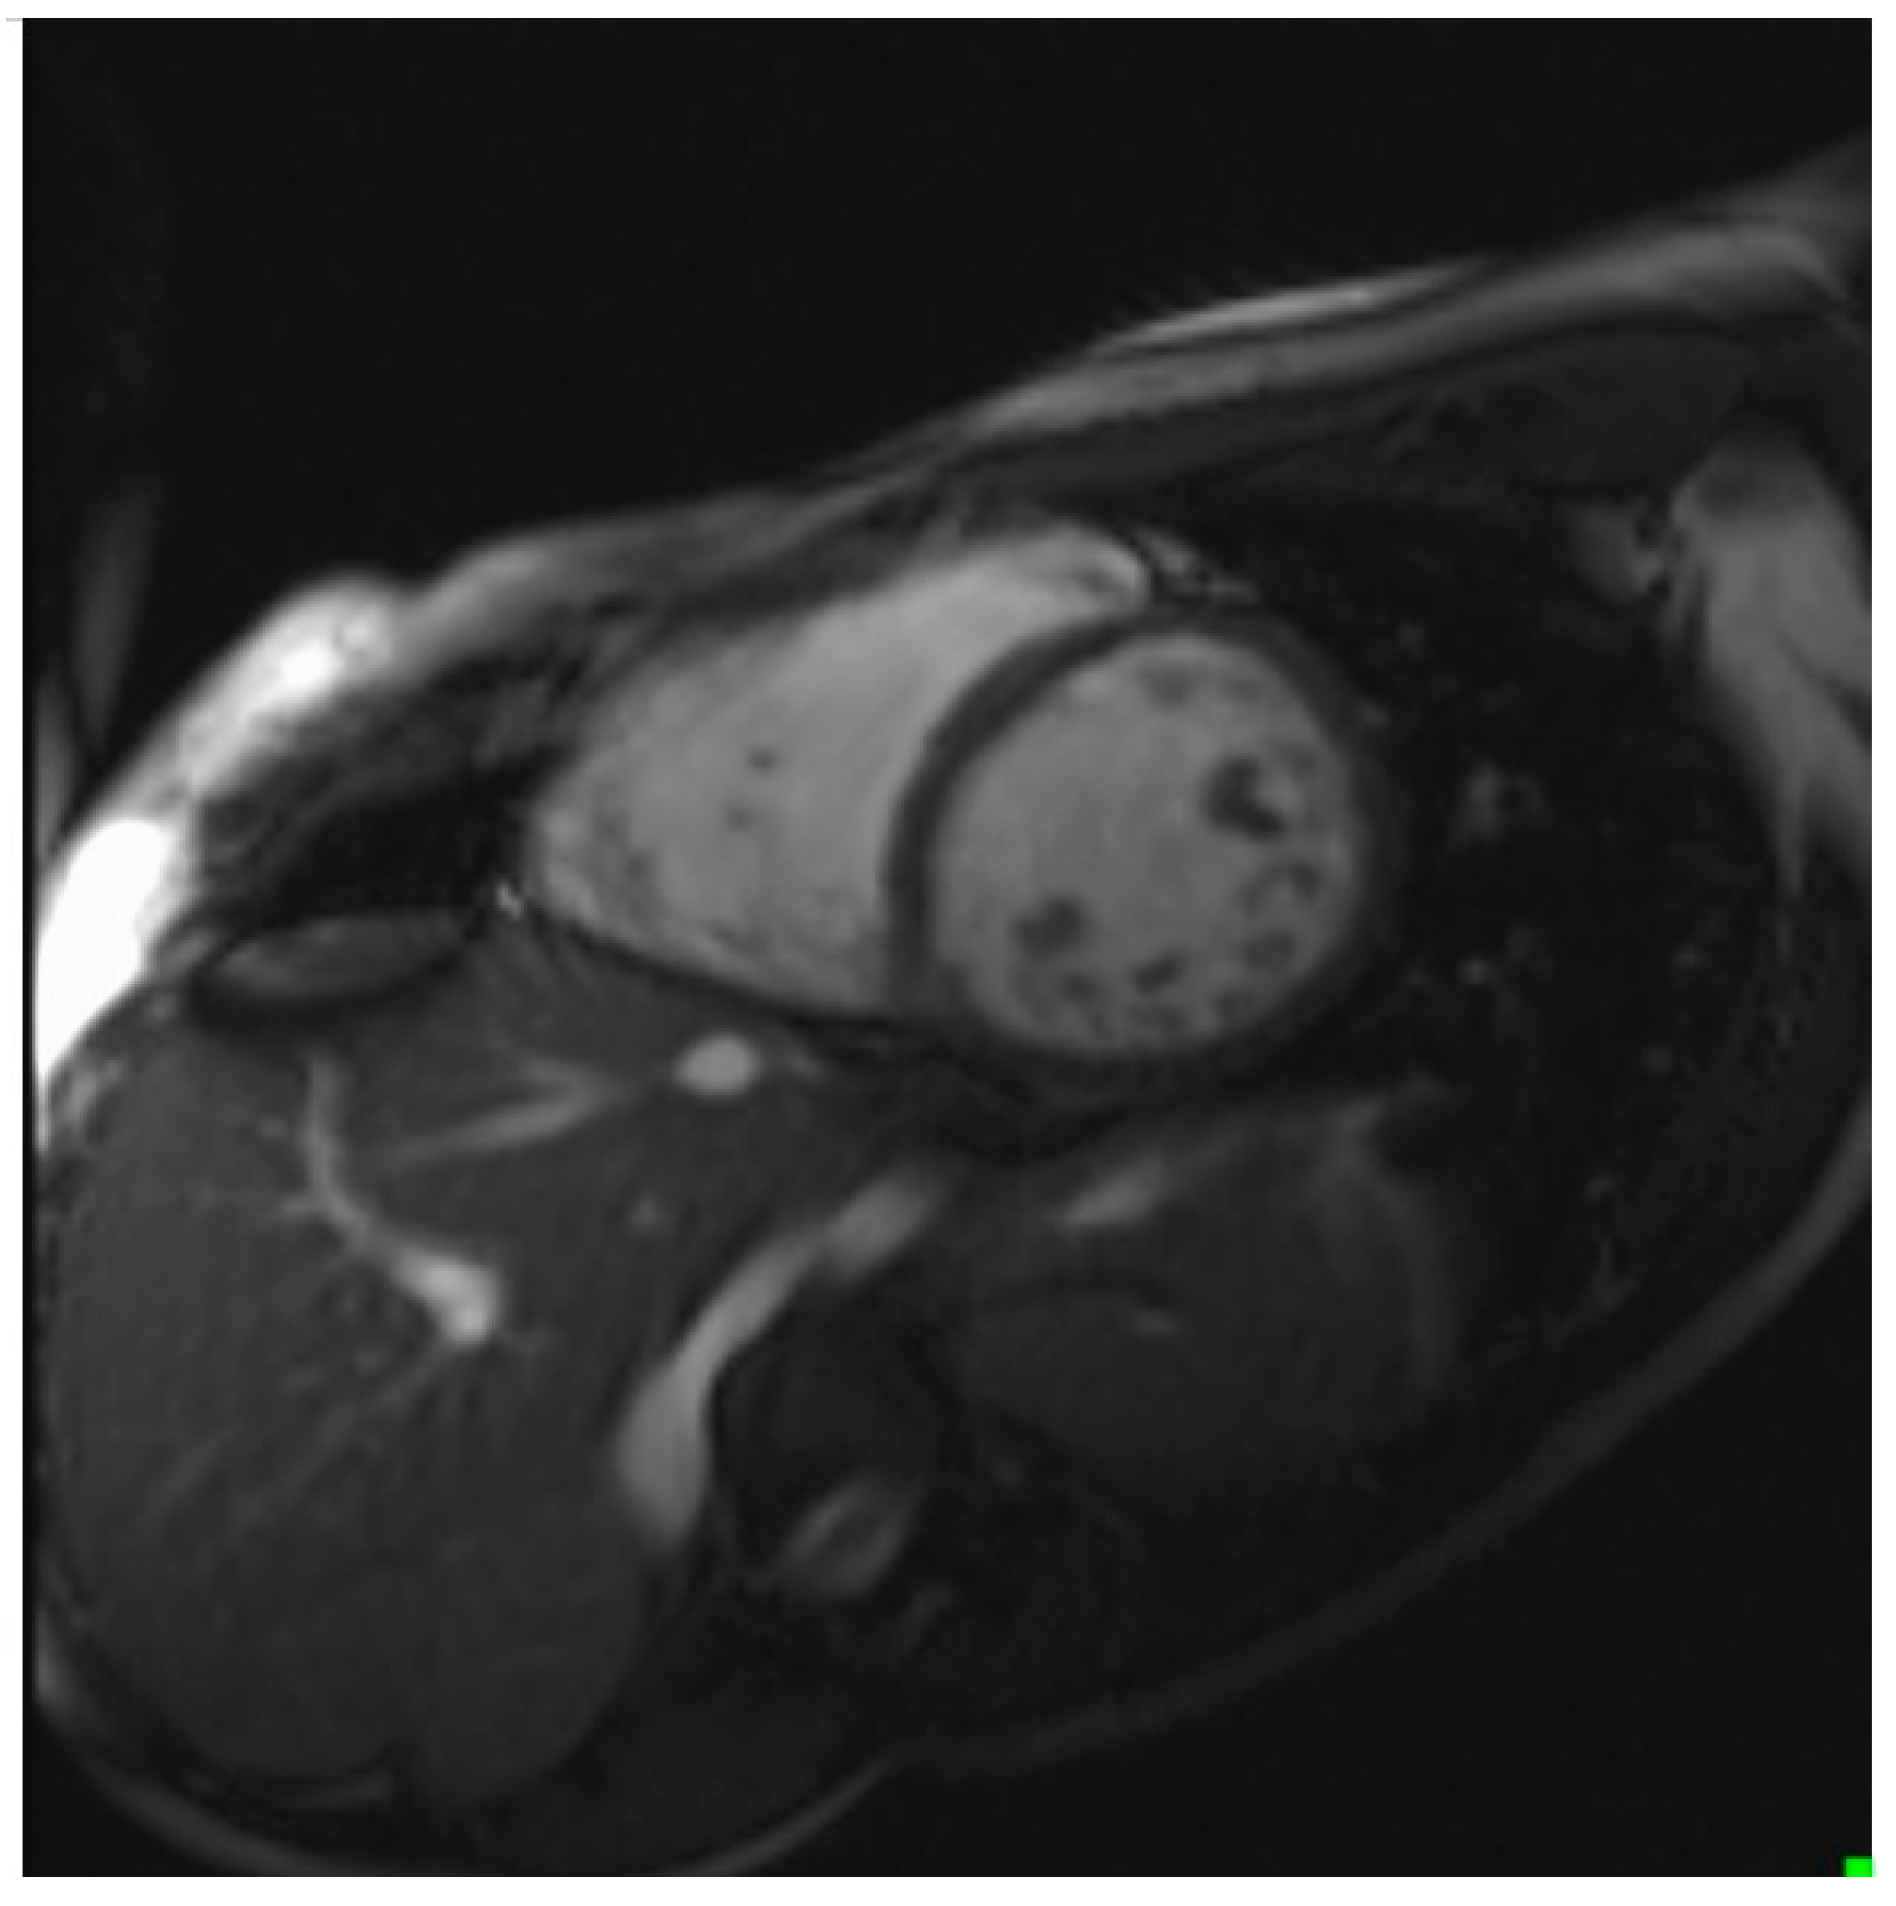

- Echocardiographic examination is the gold standard for the diagnosis of LVNC. However, cardiac CMR is recommended to confirm the diagnosis, especially in uncertain cases.

- Our results indicate that CMR has a good correlation with echocardiography and a high sensitivity and specificity in detecting non-compacted segments.